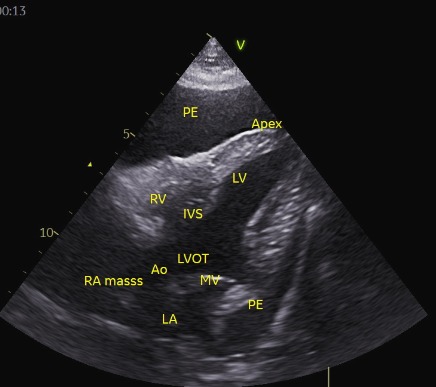

אקוקרדיוגרפיה – טמפונדה שניונית למאסה בעליה ימין.

POCUS  בית חזה הדגים pericardial effusion.

באקו לב מלא שבוצע ע״י ד״ר אסף אלקלעי, הודגמו תפליט פריקרדיאלי, מאסה בעליה ימין, התופסת את עיקר הנפח בעליה. המאסה החוסמת את זרימת דם החזרה הורידית אל העליה וממנה לחדר (הקרוס) גורמת לירידה משמעותית בתפקוד הדיאסטולי של לב ימין ולאי ספיקת לב ימין שמתבטאת ב-CVC מורחב (וג׳אגולר מורחב) כתוצאה מעליה בלחץ הדם הורידי החוזר המורגש כמו גם אחורה יותר בportal vein וכלי הדם המזנטריאליים, שם יגרום ל Portal Hypertension שיגרום לthird spacing של modified transudate לחלל הפריטוניאלי.

טמפונדה היא כבר ביטוי המודינאמי בהכרח ומוגדרת כאשר יש לחץ גדול מאוד של דם שמצטבר בחלל הפריקרדיאלי וגורם לקריסה דיאסטולית של עליה ימין ו/או החדר הימני, ומצביעה על כך שהתפליט הפריקדאלי פוגע בתפקוד הלב מהחינה מבחינה המודינמית ודורש התערבות מהירה Pericardiocentesis מונחית אקו לב מלווה באק״ג על מנת לשחרר מהר את הלחץ ולאפשר מילוי דיאסטולי.